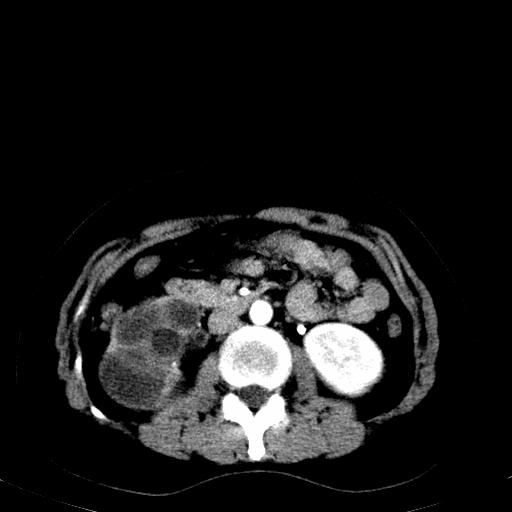

患者体检发现右肾体积增大,怀疑右肾积水

右肾重度积水,以肾盏积水明显,有分隔,上段输尿管轻度扩张,管壁增厚,考虑肾结核可能,请结合尿检查,胸部拍片排除肺结核。

右肾重度积水,建议ct向下扫描或逆行造影,左肾及左输尿管结石 .

1)不排除右肾结核可能。2)左肾及左输尿管上段结石?

结合强化图片看ivp意义不大,建议作逆行造影看一下;

左肾不是结石,是造影后改变.右肾积水,功能仅存.